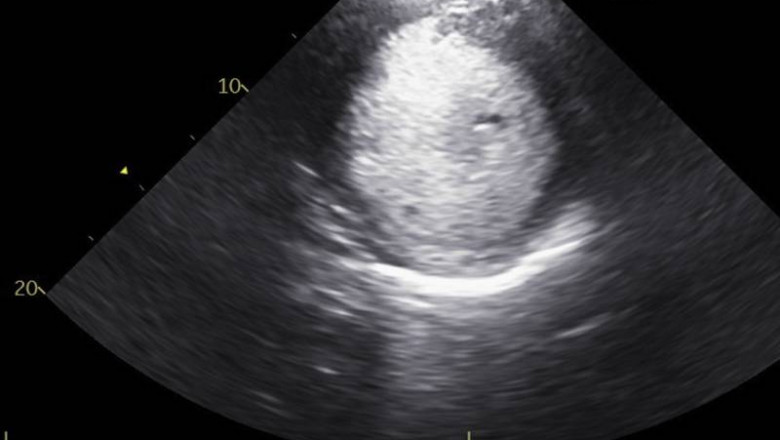

We generally hear the word ” Echocardiography” i.e. ECG in most of the hospitals or diagnostic centers but we can’t know more about the ECG Test i.e. 2D Echo test or 3D Echo Test. Why they are done? and what is the purpose of these tests? Dr. Kartik Bhosale is the best cardiologist in Pune has identified this common problem and explained in simple ways what is ECG and why it these performed?

If you are looking for the best cardiologist in PCMC and Pune area then Dr. Kartik Bhosale has the best heart specialist doctor in PCMC. He does not only treat heart disease but also gives practical advice on the prevention of heart disease. He is capable of managing all types of cardiac patients, as well as emergencies like Heart attack, heart failure, arrhythmias, etc. He explains the ECG process